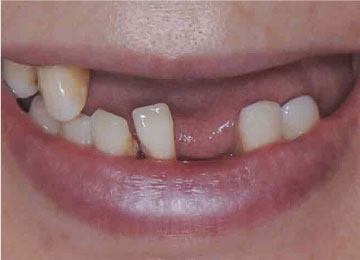

Имплантация зубов: фото «До» и «После»

Фото ДО

Фото ПОСЛЕ

All-on-4